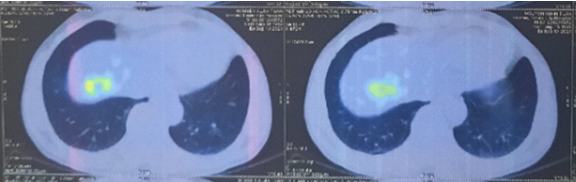

Hình 2: Vài nốt đặc nhu mô phổi 2 bên, kích thước lớn nhất 5x6mm

- PET/CT toàn thân với 18FDG:

Hình 6: Hình ảnh khối tăng chuyển hóa FDG ở thùy trên phổi trái tương ứng với tổn thương nguyên phát đã biết (vòng tròn đỏ) (cT3).

Hình 7: Chưa phát hiện hạch to, tăng chuyển hóa FDG khu trú bất thường ở trung thất – hố thượng đòn, rốn phổi 2 bên (cN0).